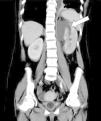

Mujer de 28 años con A. P.: esclerosis múltiple, vejiga neurógena e infecciones urinarias de repetición; sondaje vesical intermitente. Consulta por malestar general y fiebre de 38,8° C. Ingresa en UCI por sepsis grave. Se realiza ecografía abdominal que muestra patología renal izda. y TAC abdominal: vejiga con sonda e imagen alargada hiperdensa de gran tamaño que comunica con contenido hiperdenso en uréter distal izquierdo (fig. 1) (la flecha indica el cuero extraño en el interior del uréter izquierdo). Severa uretero-hidronefrosis del mismo lado y colección perirrenal con extensión a espacio subfrénico y apertura del grupo calicial superior que se comunica con el absceso. Compatible con pionefrosis con pequeños abscesos en parénquima renal y gran colección abscesificada perirrenal (fig. 2) (la flecha indica el absceso perinéfrico izquierdo). Se interpretó que la imagen en el uréter izquierdo correspondía a un cuerpo extraño, probablemente una sonda vesical introducida en alguno de los sondajes que se realizaba la paciente, rota y alojada en el uréter de forma inadvertida produciendo la uretero-hidronefrosis y los abscesos renales, como se comprobó tras la extracción de la misma. Evolución inicial: shock séptico con fracaso multiorgánico. Se trató con antibióticos, extracción del cuerpo extraño (sonda vesical) y drenaje del absceso con radiología intervencionista, intubación y ventilación mecánica. Alta de UCI 20 días después del ingreso.